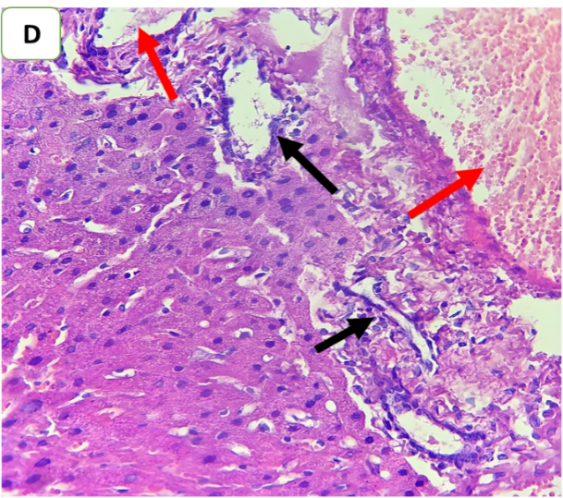

Histopathological examination was performed to evaluate the degree of hepatic injury 24 h after CLP. Compared with those in the sham group, the liver tissues in the CLP and CLP+DMSO groups were significantly damaged. Conversely, histopathological analysis of the liver in the CLP+ertugliflozin group revealed a slight degree of necroinflammation and steatosis (fig. 5, fig. 6). Fibrosis was not detected in any of the study groups.

Fig. 6: Effects of ertugliflozin on histopathological findings (6 animals in each group): A. CLP group: animals underwent CLP-induced sepsis, with a necroinflammatory grade of 3, liver tissue with vascular congestion (red arrow), hepatocytes ballooning (blue arrows), apoptotic cells (green arrow) and steatosis (yellow arrows). B. Sham group: animals in this group were anaesthetized only and then laparotomized without the induction of sepsis by CLP, and the necroinflammatory grade was zero liver tissue with vascular congestion (red arrows). C. CLP+ertugliflozin group: animals were intraperitoneally injected with ertugliflozin (20 mg/kg) 1 h before CLP, the necroinflammatory grade was zero, and vascular congestion occurred (red arrow). D. CLP+DMSO group: animals were intraperitoneally injected with DMSO (vehicle for ertugliflozin) 1 h before CLP, the necroinflammatory grade was 2, and the liver tissue exhibited mild inflammation (black arrow). Vascular congestion (red arrows). A and BandCandD X 400, HandE staining